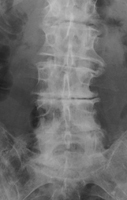

Degenerative disk disease

The presence of a linear radiolucency in the disk space (vacuum phenomenon) is a typical finding of degenerative disk disease. It is often associated to other findings of degenerative disk disease such as disk space narrowing and endplate sclerosis. Gas in the disk space is rarely associated to disk space infection.